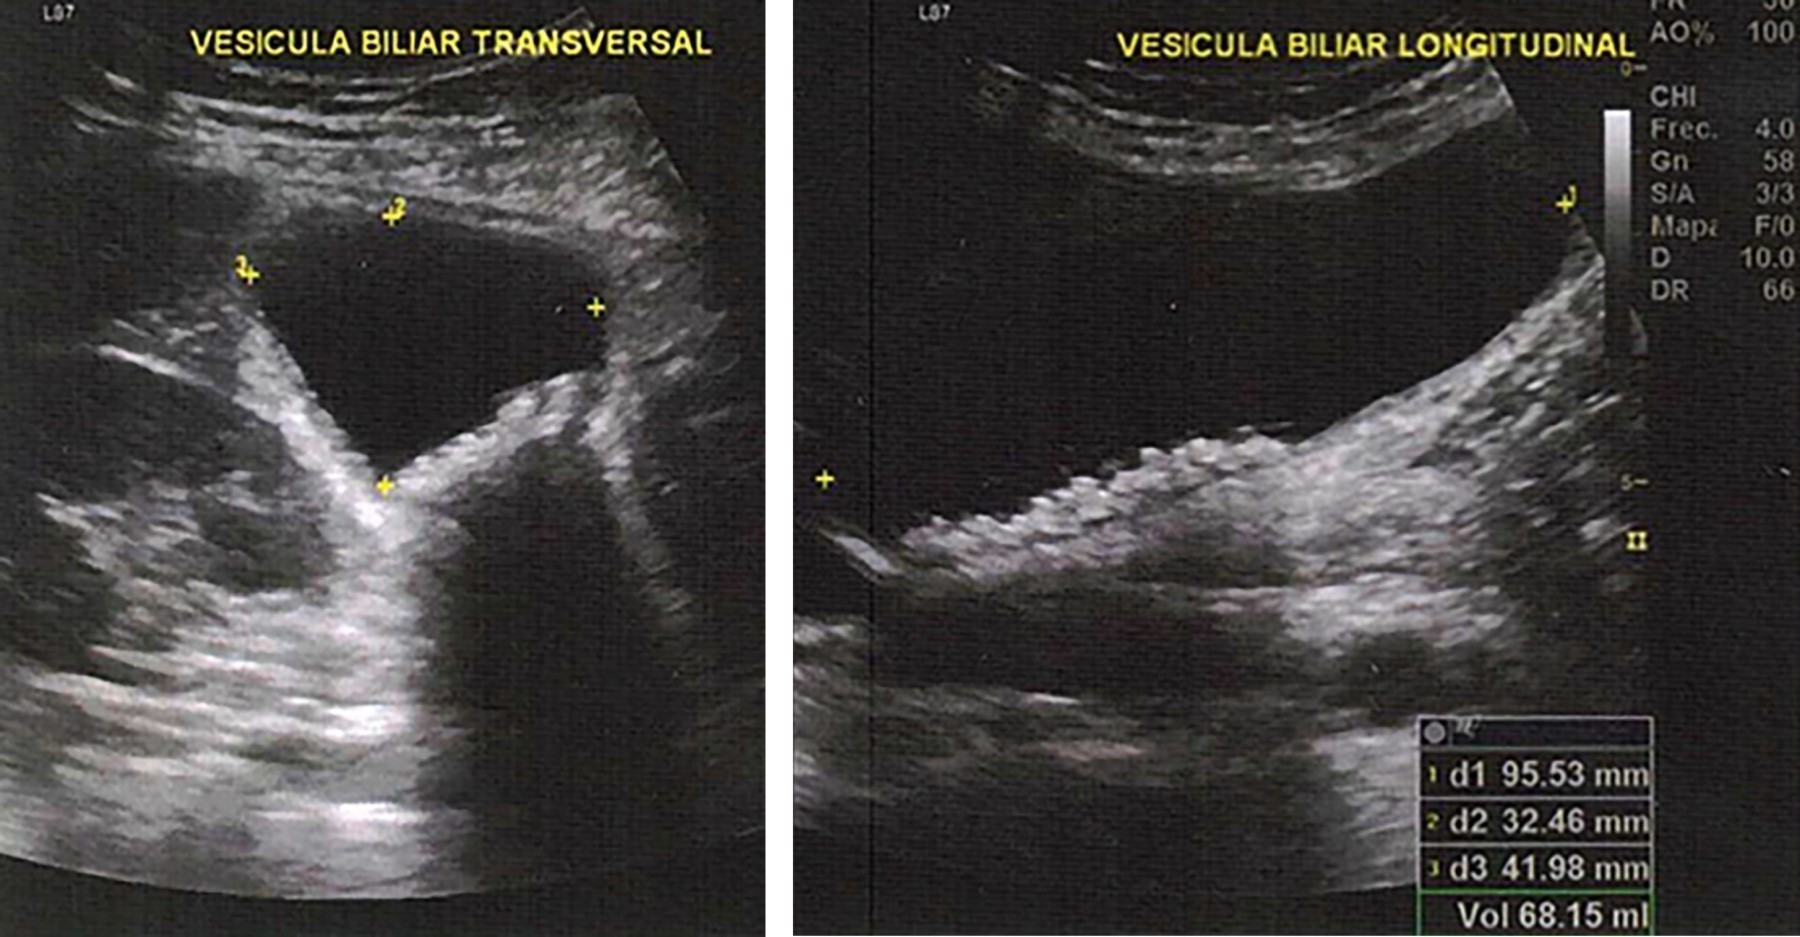

Figure 2